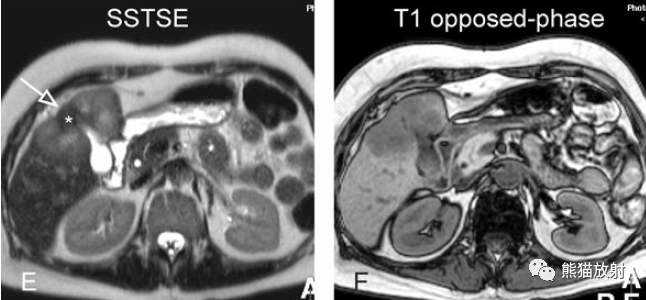

膽囊癌。病灶以膽囊為中心侵及肝臟,明顯彌散受限,由于病灶內(nèi)含結(jié)締組織/纖維成分(T2低信號)導(dǎo)致肝被膜內(nèi)陷,增強(qiáng)掃描動(dòng)脈期明顯不均質(zhì)強(qiáng)化,延遲期中心纖維成分延遲強(qiáng)化。表現(xiàn)類似肝內(nèi)膽管細(xì)胞癌。